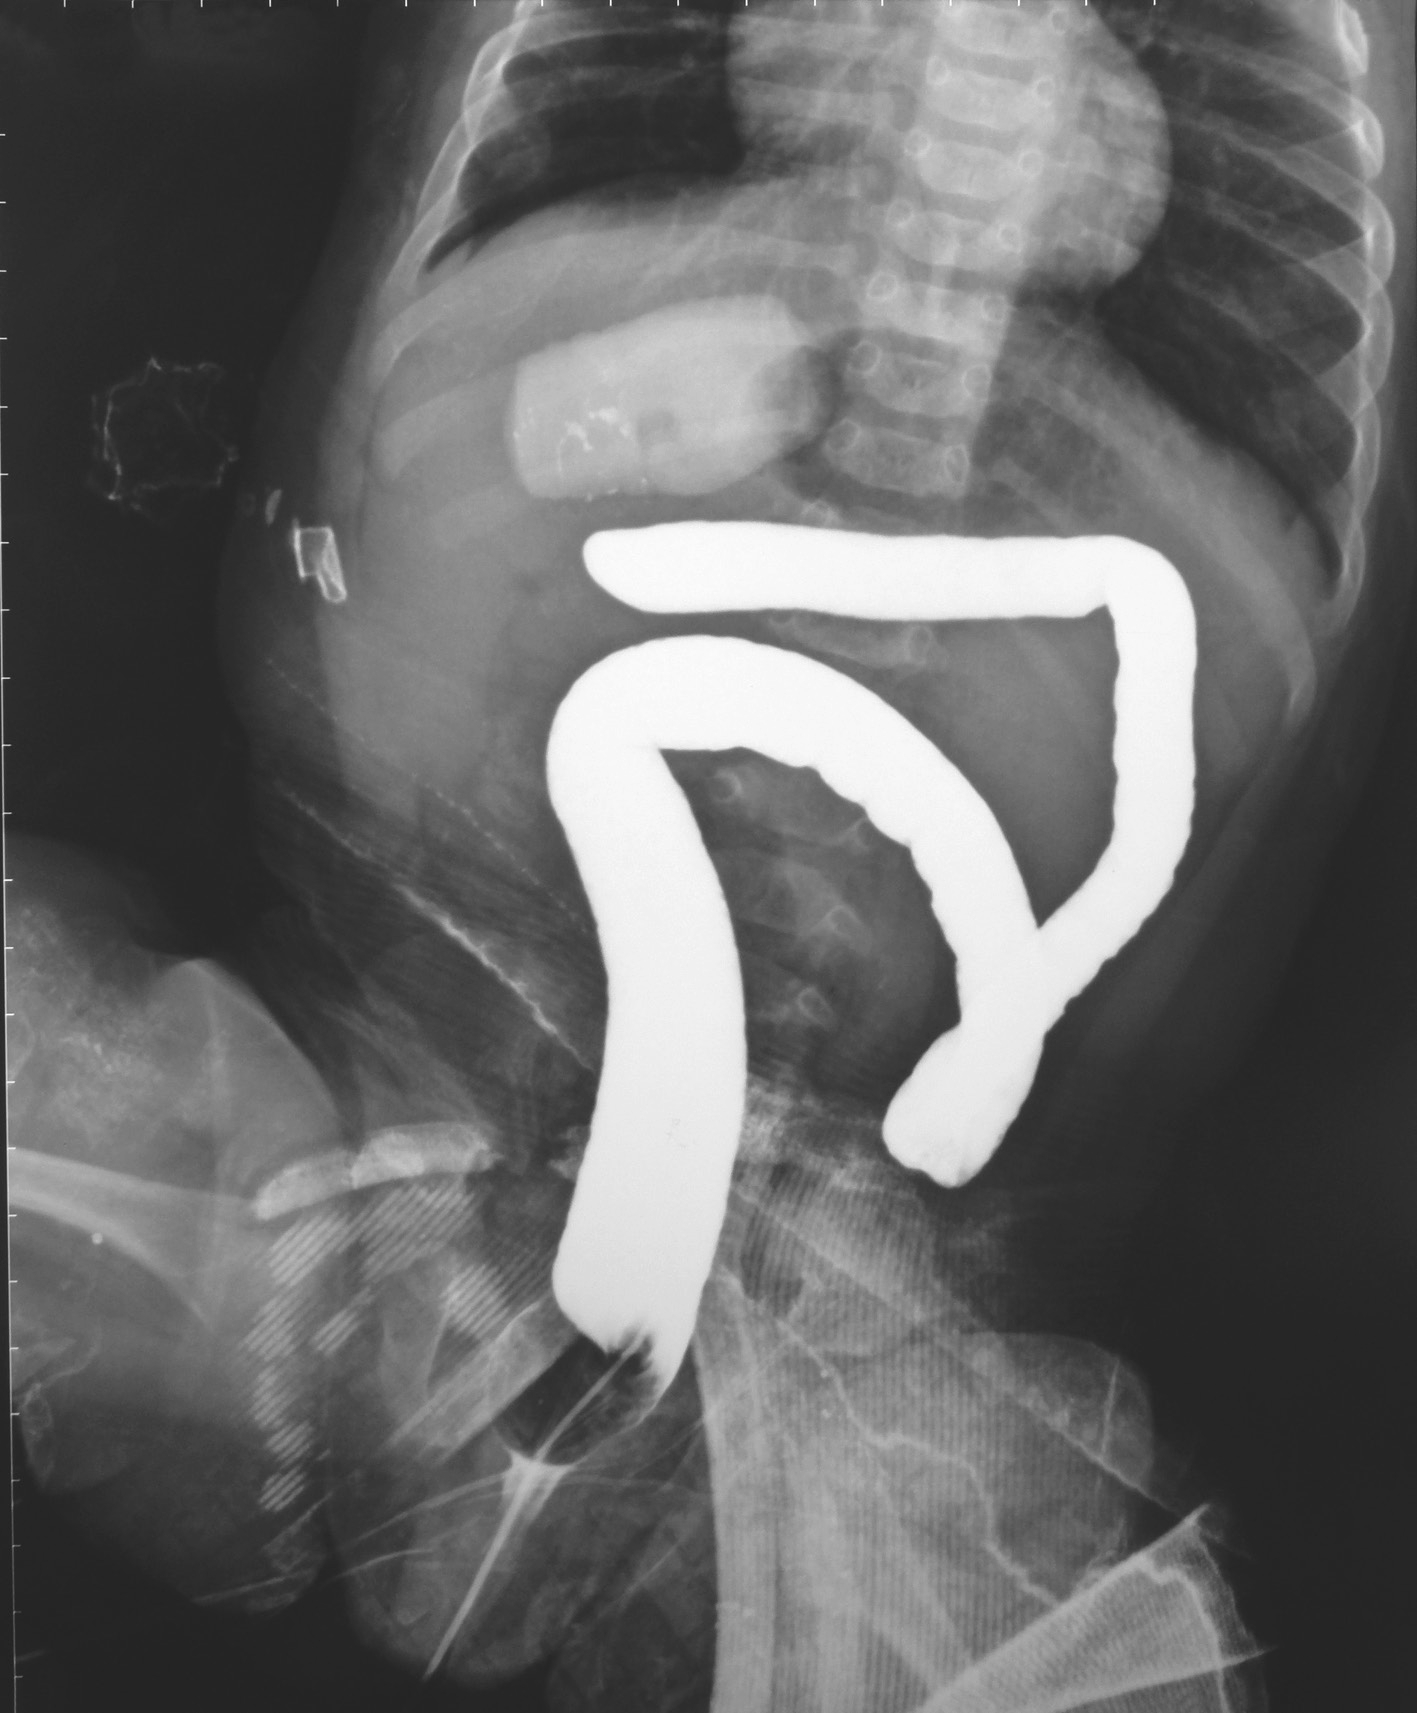

不同类型的HD钡剂灌肠检查的表现亦不同,见图3-3~图3-9。

图3-7 长段型先天性巨结肠症横结肠造瘘术后钡剂灌肠

结肠肠管如筒状,无扩张。